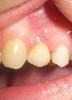

dolceragazza Опубликовано 29 декабря, 2010 Автор Поделиться Опубликовано 29 декабря, 2010 сходила к двум имплантологам, один, не делая снимка, сказал, что боль из-за того , что рано поставлена коронка и 50/50 , что имплант отторгнется. второй сделал снимок , посмотрел постучал, сказал, что подвижности нет, имплант стабилен, и боль из-за того, что неправильно зафиксирована коронка и десна попадает между имплантом и самой коронкой. к сожалению, врач- ортопед вернется только 12 января терпит ли ситуация или надо срочно принимать меры?извините за кач-во фотоспасибо Ссылка на комментарий

Aldo Rain Опубликовано 29 декабря, 2010 Поделиться Опубликовано 29 декабря, 2010 (изменено) по снимку с имплантатом все нормально, а вот коронка вроде не досажена+разобраться с 5-кой надо Изменено 29 декабря, 2010 пользователем lekar12 Ссылка на комментарий

Doc Опубликовано 29 декабря, 2010 Поделиться Опубликовано 29 декабря, 2010 Есть ощущение, что недосажена не коронка, а абатмент. В любом случае надо досаживать. Ссылка на комментарий

Doc Опубликовано 29 декабря, 2010 Поделиться Опубликовано 29 декабря, 2010 И еще один момент, там кусок цемента торчит, его надо вынуть. Из-за него боли могут быть очень даже! Ссылка на комментарий

dolceragazza Опубликовано 29 декабря, 2010 Автор Поделиться Опубликовано 29 декабря, 2010 И еще один момент, там кусок цемента торчит, его надо вынуть. Из-за него боли могут быть очень даже! такое белое пятно около десны? извените за дилетантский вопрос, откуда он мог там взяться? не скажет.ткнете пальчиком в снимок. прямо в темную щель между частями конструкции - ее (щели) быть не должно. странно, что он сам не увидел этого Ссылка на комментарий